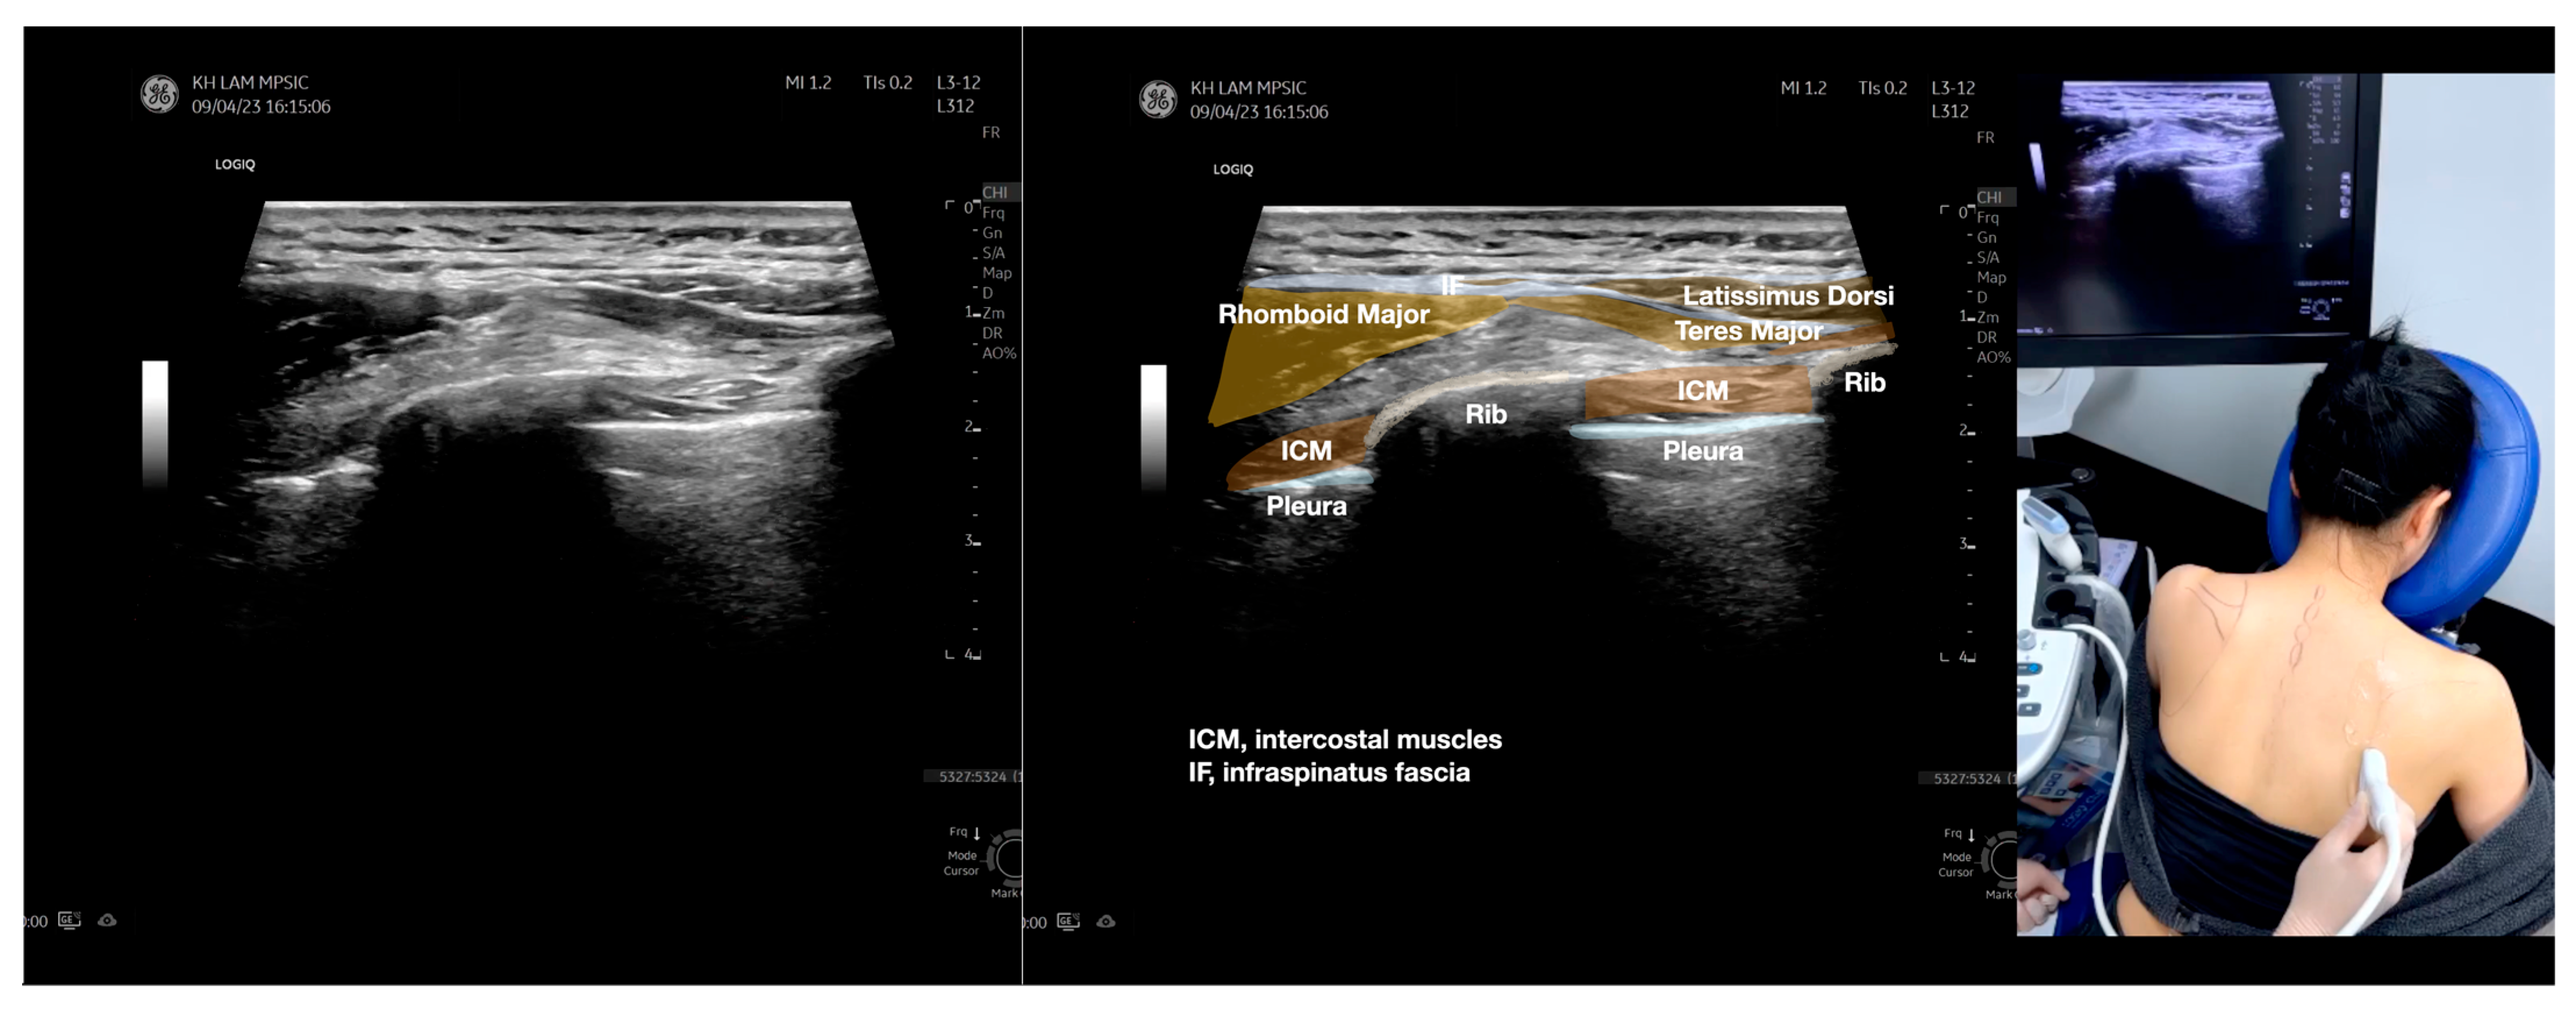

Figure 5.

Sonoanatomy of scanning the infraspinatus fascia in the sagittal plane from the rhomboid minor laterally, then back to the rhomboid major. The step-by-step scanning techniques of the structures illustrated in this figure have been shown in Video S9. Available online: https://www.dropbox.com/s/gu9hhrdq9erin6n/Figure%205.docx?dl=0 (accessed on 1 January 2023).